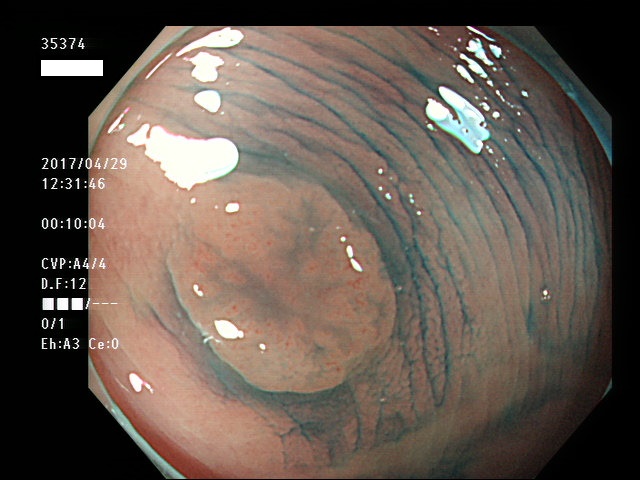

上記100名より抽出した平坦・陥凹型腺腫・SSAP(=癌化の危険が高いが見落としやすい病変)の内視鏡写真